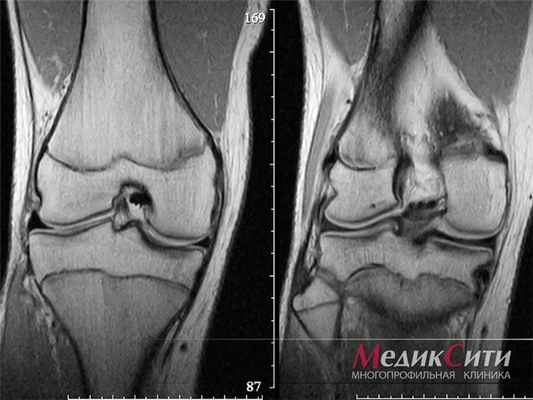

(Слева) При МРТ в аксиальной плоскости на Т1 ВИ определяется слабо гетерогенное образование, изоинтенсивное по сравнению с прилежащими мышцами. Образование, располагаясь в глубоких отделах ладони, смещает сухожилия сгибателей и срединный нерв.

(Справа) При МРТ с контрастным усилением в аксиальной плоскости на Т1 ВИ в режиме FS выявленное образование характеризуется узловым характером контрастирования. При этом зона в центре контрастируется слабо. При резекции в данной зоне был обнаружен миксоидный субстрат, встречающийся относительно редко. (Слева) У этого же пациента при МРТ в аксиальной плоскости на Т2 ВИ в режиме FS выявленная фиброма сухожильного влагалища характеризуется преимущественно гиперинтенсивным сигналом и содержит лишь несколько зон, изоинтенсив ных по сравнению с мышцами.

(Справа) При МРТ в аксиальной плоскости на ППВИ с медиальной стороны заднего отдела стопы визуализируется образование, характеризующееся изоинтенсивным сигналом по сравнению с мышцами и наличием в центре волнистой гипоинтенсивной зоны. На медиальной поверхности ладьевидной кости выявляются эрозивные изменения. (Слева) У этого же пациента при МРТ в аксиальной плоскости на Т2 ВИ выявленное образование характеризуется гиперинтенсивным сигналом по сравнению с мышцами и наличием в центре гипоинтенсивной зоны. Образование прилежит к сухожилию задней большеберцовой мышцы, диффузно утолщенному вследствие тендиноза.

(Справа) При МРТ с контрастным усилением в аксиальной плоскости на Т1 ВИ выявленная фиброма сухожильного влагалища характеризуется выраженным контрастированием за исключением гипоинтенсивной зоны в центре, вероятно, соответствующей плотной ткани коллагенового типа.